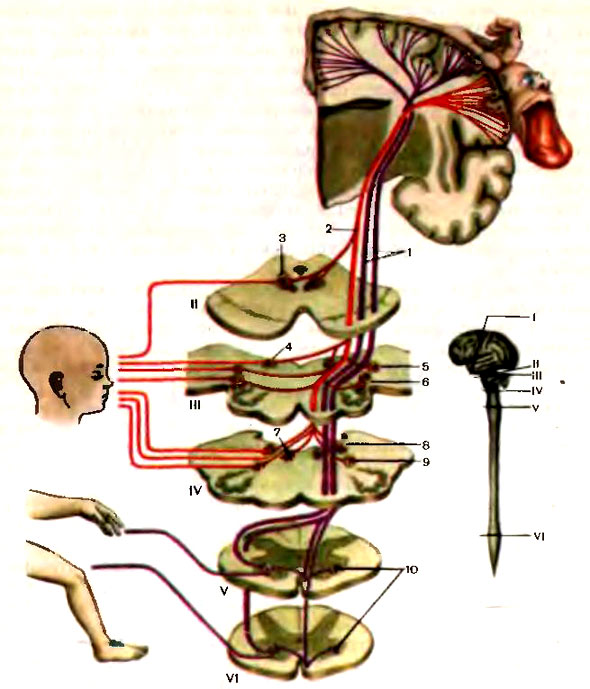

Пирамидная симптоматика в неврологии: ключевые аспекты